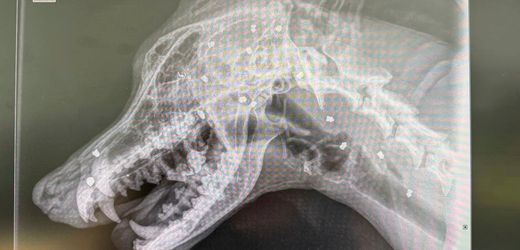

Bautzen: Hund überlebt 42 Kopfschüsse – Ermittlungen gegen Herrchen

Ein Hund in Bautzen ist mit Dutzenden Projektilen aus einem Luftgewehr verletzt worden. Die Polizei ermittelt jetzt gegen das ehemalige Herrchen. Der Vierbeiner befindet sich auf dem Weg der Besserung und hat einen neuen Namen.